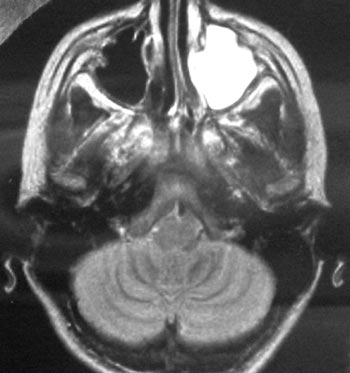

Εικόνα 3. MRI (3ο 24ωρο):

εκτεταμένη συλλογή πύου στο αριστερό ιγμόρειο.